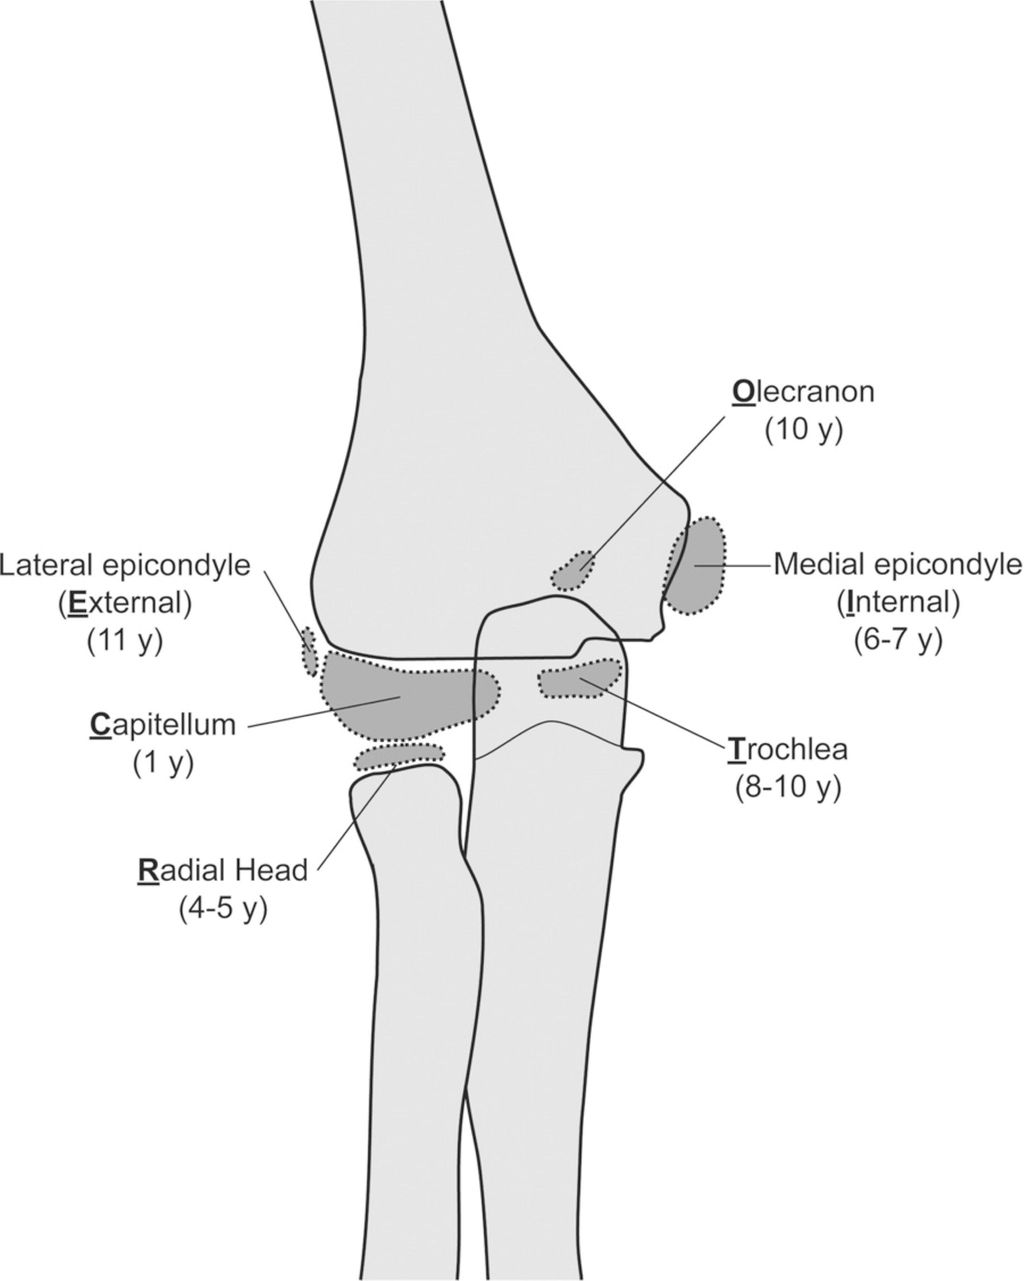

Der Ellbogen des Jugendlichen stellt weiterhin spezifische Herausforderungen im klinischen Alltag dar. Die Interpretation des einfachen Röntgens wird durch die multiplen Knochenkerne erschwert. Zum Glück treten diese in verhältnismässig geordneter Reihenfolge jährlich entsprechend dem Merkwort CRITOE (Capitellum – Radiuskopf – innerer (medialer) Epicondylus – Trochlea – Olekranon – externer [lateraler] Epicondylus) entsprechend den ungeraden Zahlen 1–11 auf. (Abb. 2). Sie verschmelzen mit dem Humerus zwischen dem 12. und 16. Lebensjahr, wobei Capitellum, Trochlea und lateraler Epicondylus gleichzeitig fusionieren, gefolgt von Radius, Olekranon und zuletzt medialer Epicondylus. Das heisst, wenn der Knochenkern des Olekranon sichtbar ist, der mediale Epicondylus aber nicht, dann handelt es sich mit hoher Wahrscheinlichkeit um eine dislozierte Fraktur und der oder die Patient:in hat ein (Knochen-)Alter von ungefähr 9 Jahren. Sieht man eine Aufhellung am medialen Epicondylus, aber die Wachstumsfuge des lateralen Epicondylus ist auch zu sehen, so liegt mit hoher Wahrscheinlichkeit keine Fraktur vor.